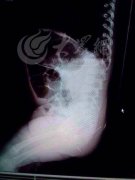

2014年,山东聊城一名11月大的女婴子萱(化名)被发现体内有12根钢针,随后嫌疑人萱萱的舅妈服毒自杀,案件以此画上句号。2015年7月22日,女婴被扎12钢针的取针视频被公布,再度引发公众关注。女婴被扎12钢针,疑似舅妈下毒手,之前已经服毒自杀。女婴被扎12钢针,在北京儿童医院9科专家共同手术5小时之后,12根钢针一次性取出,没有留下后遗症。术后返院复查也显示女婴恢复良好。医生在B超、腹腔镜等工具的配合下,小心翼翼地从子萱的大腿、脾脏、肾脏等各处取针。更让人惊讶的是,取出的12根钢针,除了2根是常用的绣花针,其他的10根都是半截的医用注射器针头。

女婴被扎12钢针 还记得2014年山东聊城女婴被扎12钢针事件吗?7月22日,女婴被扎12钢针的取针视频被公布,再度引发公众关注。女婴被扎12钢针,疑似舅妈下毒手,之前已经服毒自杀。女婴被扎12钢针,在北京儿童医院9科专家共同手术5小时之后,12根钢针一次性取...